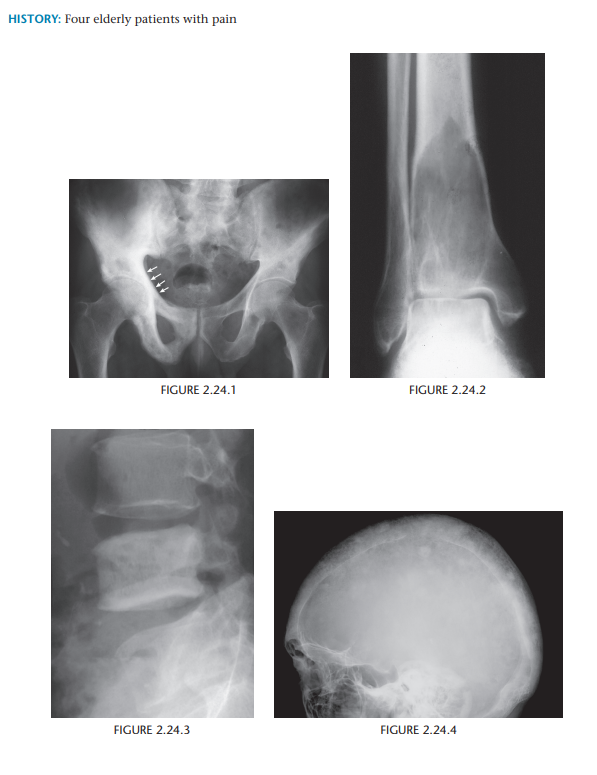

Paget’s Disease

Characteristic, but not entirely pathognomonic, patterns of Paget disease include the flame-shaped lucency within the long bones, the “ivory” and “picture

frame” vertebral body, and osteoporosis circumscripta or cotton-wool appearance of the skull